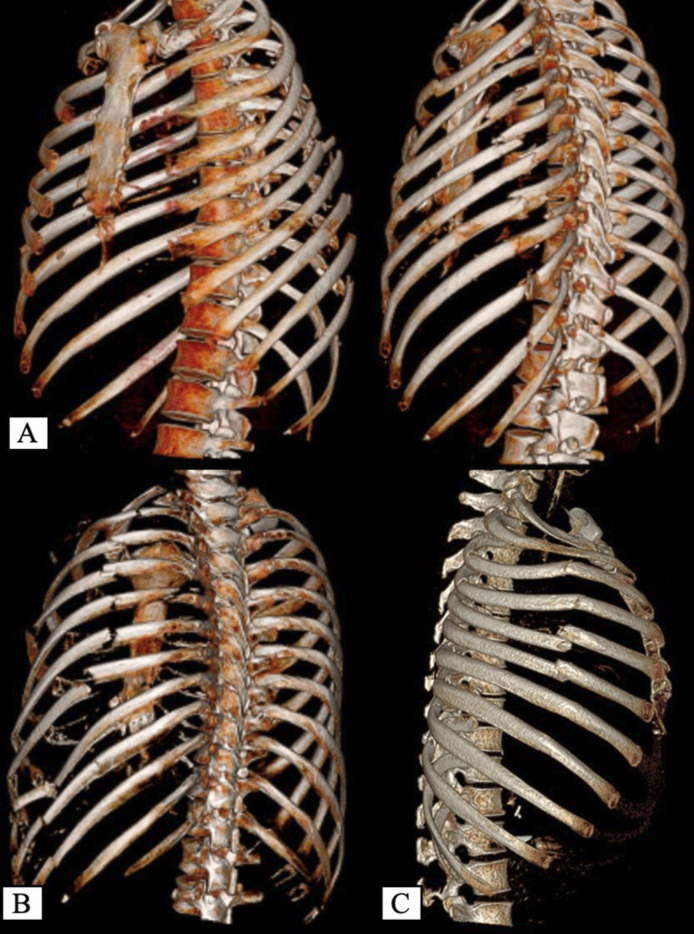

Abstract Image